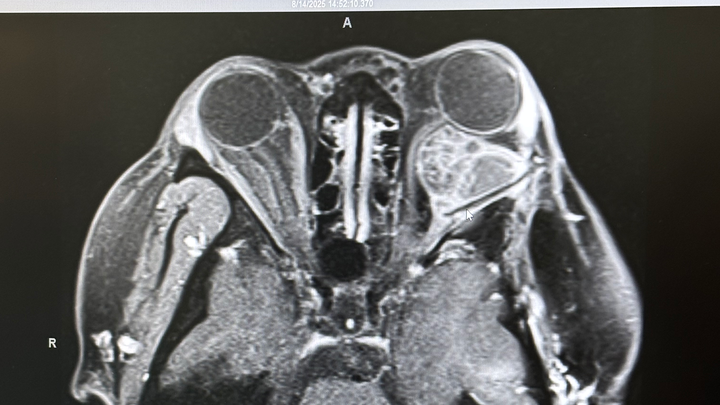

In Jan 2023 noticed I was having double vision very bad. After my monthly MRI my ENT Dr asked for more DNA testing on my tumor from 2022. They came back with the discovery of the BRAF V600E mutation. This time it was on the optic nerve of my left eye and this was why I was having double vision.

Eventually in Summer 2025 it was time to discuss what I had been avoiding for years EYE SURGERY I have done everything I can to avoid surgery on my "perfectly working eye" I look past the double vision (I still have a mild case), watery eye, light sensitivity (im not wearing sunnies in the club during my parties trying to be cool lmao i literally can not see!), the bulging (i don't even wear makeup anymore i hate it not even mascara or lashes), etc. The more I looked at my scans and how this thing is literally latched on to the nerve(s) attached directly to my eyeball I could lose my vision at any moment tbh ♀️ so possibly losing it because of the surgery is a risk I am willing to take to remove this thing and move on with my life.